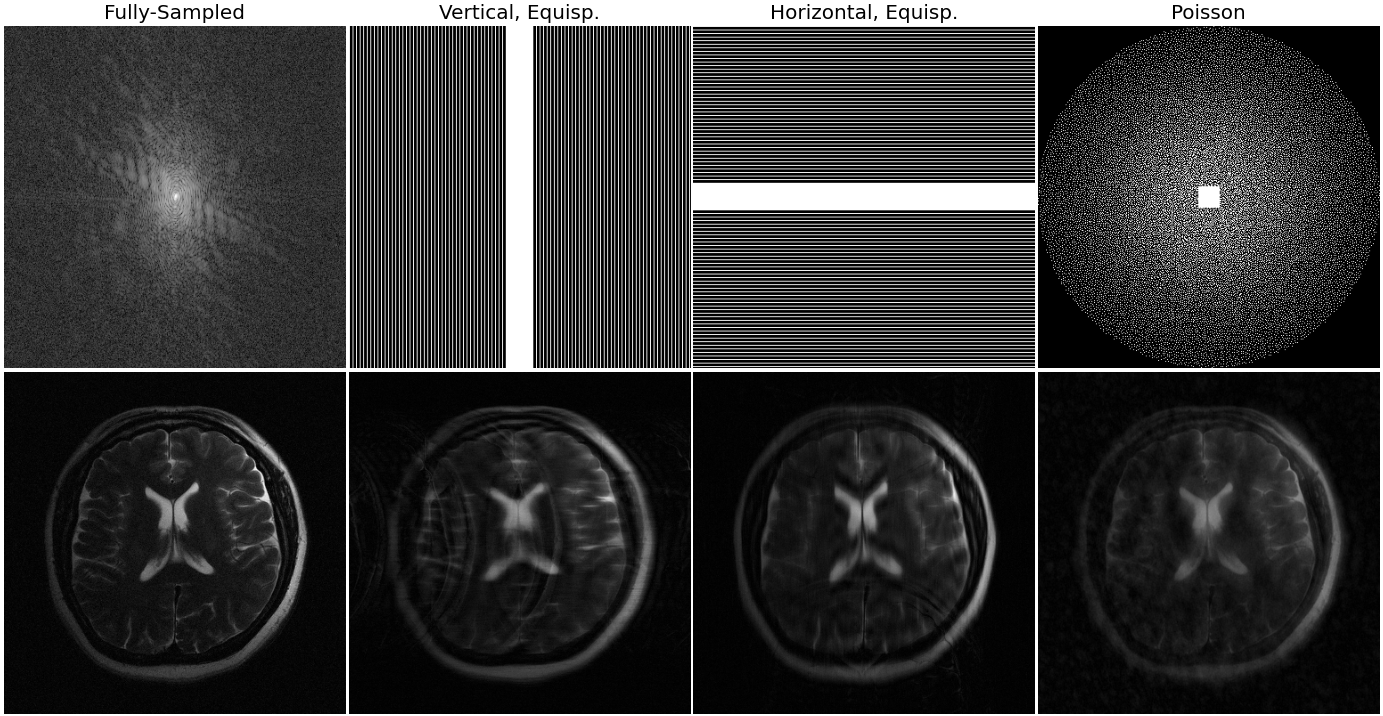

In this experiment, we test all models using the same forward model that matches the training conditions for the baselines: vertical, equispaced sampling patterns. Examples of various sampling patterns are shown in Appendix C.

Here we consider shifts in the forward sampling operator at test-time, while still evaluating on the same anatomy as the training conditions. We measure robustness by evaluating the average incurred performance loss when the sampling pattern changes. Recall that our proposed approach does not use any explicit information about the sampling pattern P𝑃P during training, hence we anticipate the highest degree of robustness.